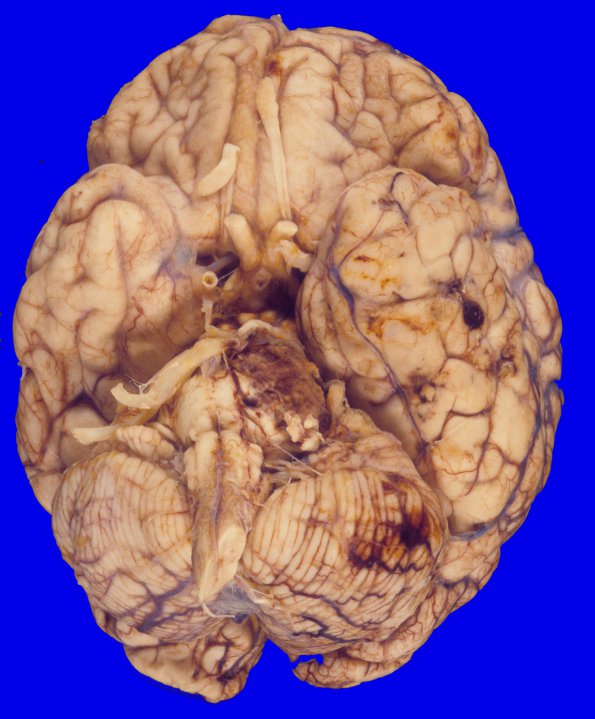

32A1,2 There is a subarachnoid hemorrhagic area on the left temporal lobe surface, measuring I cm in greatest surface dimension. There are several hemorrhagic lesions involving the left temporal lobe. The hemorrhagic area in the left temporal lobe is a superficial hemorrhagic infarct with surrounding gliosis, vascular proliferation and hemosiderin laden macrophages.